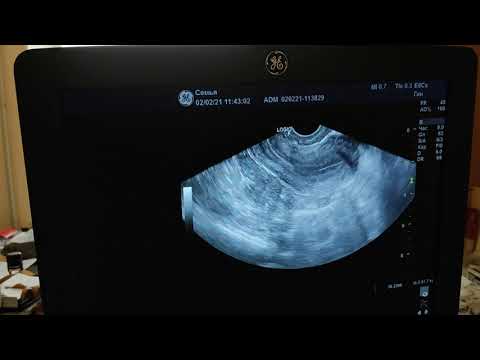

УЗИ малого таза

УЗИ органов малого таза в норме

УЗИ малого таза (трансабдоминальное исследование)